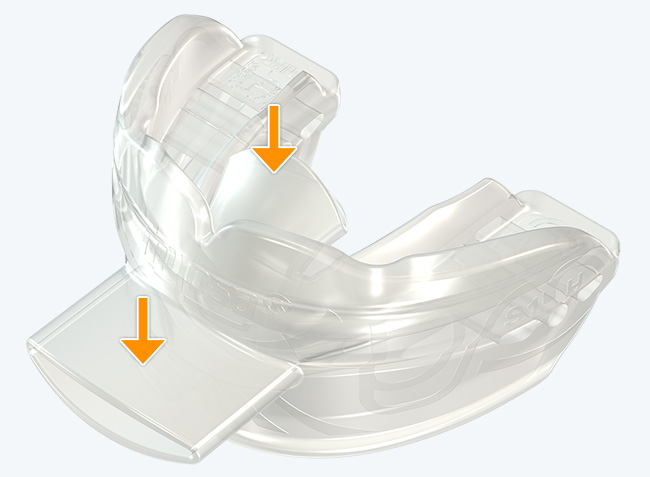

Myosa® for TMJBDS® Stage 1 Hybrid - S1H

Establish a functional airway and permits active exercises

The Myosa® for TMJBDS® S1H is specifically designed for patients who are breathing and disordered sleep (BDS) primary with moderate to severe BDS as indicated by a Breath Hold Time (BHT) of 20 or less. These patients may or may not have TMJ disorders, but due to the severity of their BDS, they require immediate improvement of their airway. The features of the appliance not only work to open the airway, but also allow patients to undertake initial exercising of the lip, tongue and airway muscles. Progress to the S1 when the patient’s BHT reaches 20 seconds or more.